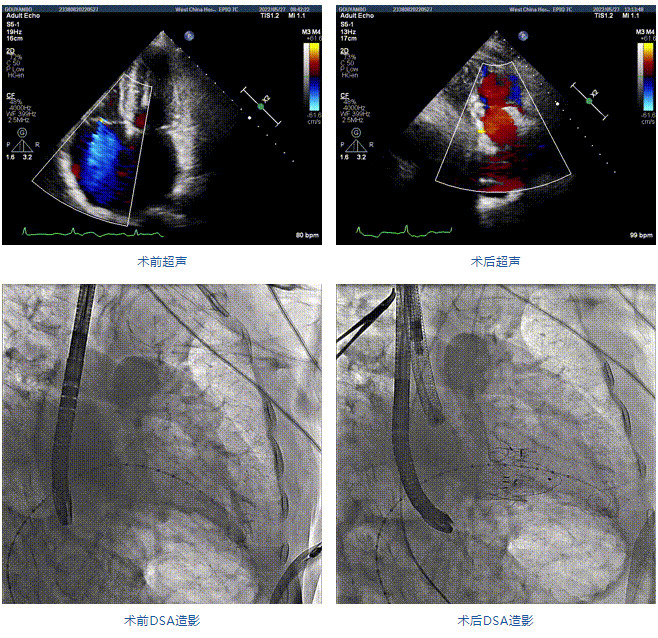

2022年5月27日,四川大學(xué)華西醫(yī)院心臟內(nèi)科陳茂、馮沅教授帶領(lǐng)的瓣膜病介入治療多學(xué)科團隊,在國內(nèi)首次采用純介入方式通過穿刺右側(cè)頸靜脈成功完成經(jīng)導(dǎo)管三尖瓣置換。植入的人工瓣膜是具有中國自主知識產(chǎn)權(quán)的LuX-Valve Plus系統(tǒng)。術(shù)中上海長海醫(yī)院陸方林教授和喬帆副教授給予了在線支持。

患者為89歲高齡男性,罹患三尖瓣反流多年,近期癥狀明顯加重,經(jīng)過充分的藥物治療后仍然存在嚴重心力衰竭。通過純介入方式實施三尖瓣置換,使這位超高齡的老人以最小的代價獲得了有效的治療。介入治療的效果十分滿意,術(shù)后三尖瓣反流消除,老人迅速恢復(fù),心功能明顯改善。該手術(shù)的成功實施標(biāo)志著國內(nèi)經(jīng)導(dǎo)管三尖瓣置換進入純介入時代。

89歲男性。術(shù)前超聲報告顯示:雙房增大,左室壁肥厚,主、肺動脈增寬,三尖瓣重度反流。

團隊前期經(jīng)過多次討論,制定了周密的手術(shù)策略和預(yù)案。由于患者已是近九旬的超高齡老人,傳統(tǒng)外科開胸手術(shù)風(fēng)險極高,純介入經(jīng)血管三尖瓣替換能夠明顯減少創(chuàng)傷。術(shù)中陳茂及馮沅教授結(jié)合體表定位在造影指示下精準(zhǔn)穿刺右側(cè)頸靜脈并預(yù)置兩把血管縫合器。成功建立經(jīng)皮血管入路后在食道超聲和DSA的引導(dǎo)下順利完成人工瓣膜植入,術(shù)后超聲和造影顯示人工三尖瓣同軸性良好,瓣架固定牢靠,無反流和瓣周漏,平均跨瓣壓差降為1mmHg。術(shù)畢收緊預(yù)置的血管縫合器縫線完成止血,縫合效果滿意,在手術(shù)室即刻拔除氣管插管。